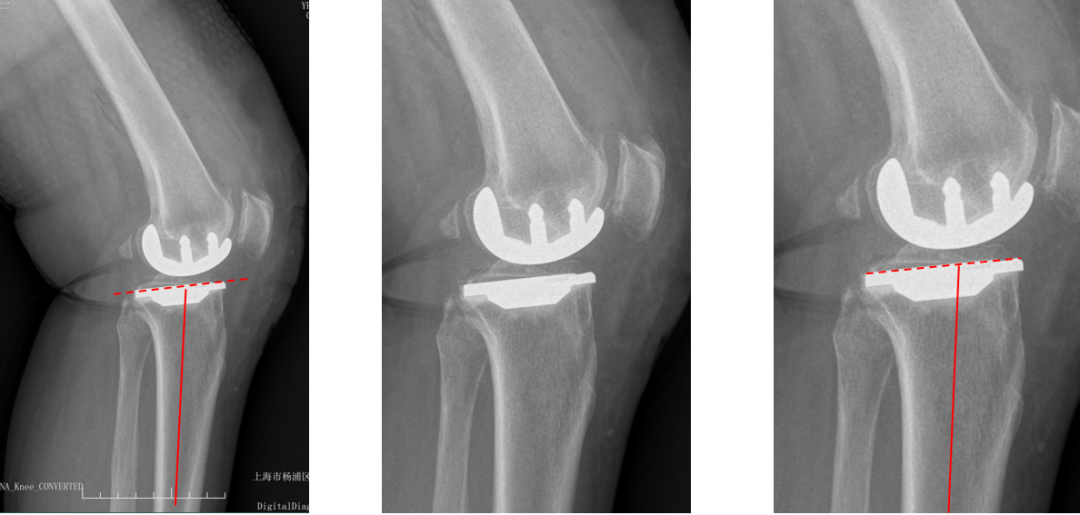

胫骨假体内翻

AP位胫骨与股骨假体位置:胫骨假体内翻10°,股骨假体中轴线与胫骨假体垂直。

胫骨假体后倾角大

侧位胫骨假体位置:胫骨假体后倾11°,前后缘齐平。

胫骨假体前倾

侧位胫骨假体位置:胫骨假体前倾5°,前后缘齐平。

股骨假体后倾不足

侧位股骨假体位置:股骨假体后倾5°,后髁包容不足。